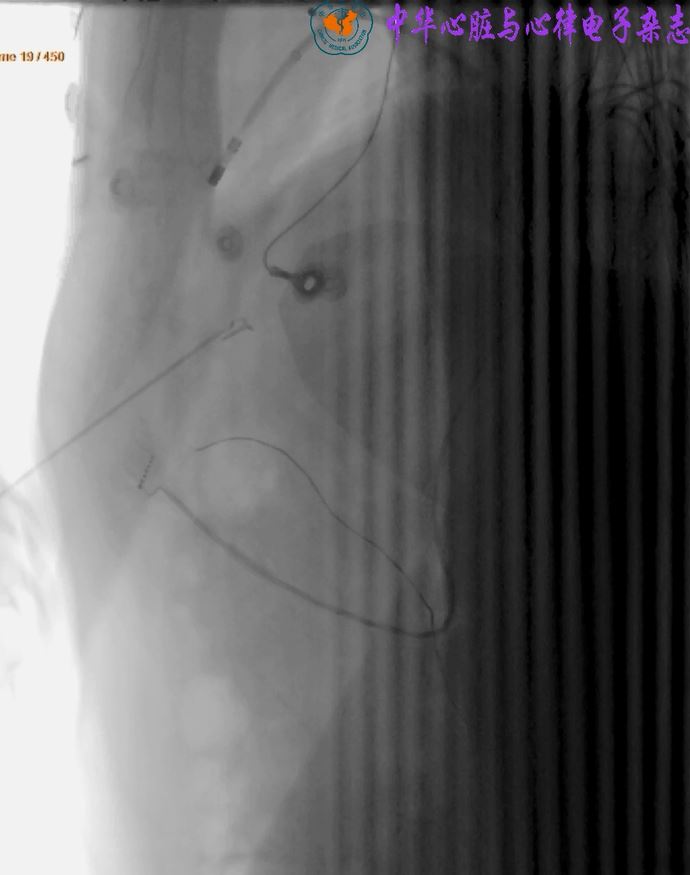

无导线起搏器植入操作视频

李若谷, 张魏巍

中华心脏与心律电子杂志 2022 , 10 (02) : 123 -124 .